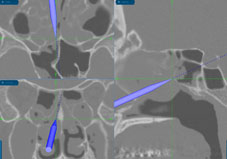

雙重保險-「鼻竇導航手術」

自從內視鏡鼻竇手術風行開始,為追求手術更細緻安全,使用導航系統輔助手術的概念便逐漸形成。在沒有導航的時代,醫師只能靠閱讀術前影像,在腦中建立起病患的鼻竇立體結構,搭配解剖知識及手術經驗去執刀。

但即使醫師技術再熟練,臨床上仍會遇到較複雜嚴重的病例,於是我們需要雙重保險來確保手術安全,以避免併發症。鼻竇導航手術的問世,便是為了因應對於手術精準和安全更嚴格的要求;它的運作原則很簡單,手術時醫師的器械到那裡,3D影像就要同時呈現當時的位置;換句話說,有了這套系統,鼻竇地圖不僅預先建構在醫師的腦海裡,也即時呈現在手術螢幕上,就像開車使用衛星導航一樣。

即使導航系統問世至今還沒有很久,但2002年美國耳鼻喉科醫學會已經提出共識,建議許多狀況適用鼻竇導航手術,以避免術後視神經、眼外肌傷害或腦脊液滲漏等併發症。

導航系統的即時鼻竇影像